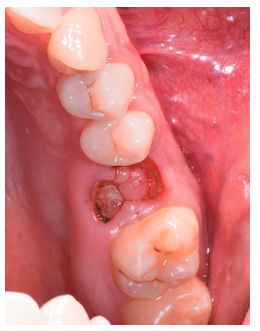

Tras obtener el consentimiento informado, se realizó un bloqueo anestésico mediante Articaína al 4% con adrenalina 1:100.000 (Ultracain®, Normon SL, Madrid, España) del nervio alveolar superior posterior y medio, y palatino anterior. Se realizó la extracción de forma atraumática de los restos radiculares del 2.6 y el legrado del proceso apical (Figura 6), dejando el alveolo del 2.6 preparado para recibir el autotrasplante del 2.8 (Figura 7).

Se procedió entonces a la extracción del 2.8 con fórceps (Figura 8), manipulando mínimamente el ligamento periodontal del tercer molar, colocando el tercer molar superior en la posición del primer molar superior (Figuras 9 y 10).